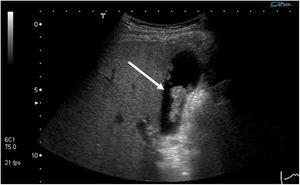

| Cholesterol polyp | Cholesterol deposits in the interior of the macrophages in the lamina propia of the gallbladder wall | Hyperechoic structure, no posterior acoustic shadow, and does not vary position with patient movement (Fig. 1) |